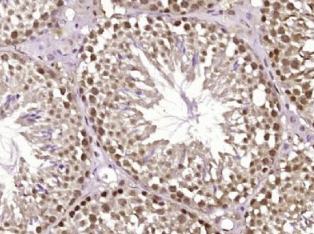

多聚甲醛固定,石蜡包埋(小鼠睾丸组织);用柠檬酸钠缓冲液(pH6.0)煮沸15min后获得抗原;用3%过氧化氢阻断内源性过氧化物酶20分钟;阻断缓冲液(正常山羊血清)37℃30min;抗体(ACS)多克隆抗体1:40孵育。0在4°C下过夜,然后根据SP试剂盒(兔子)说明和DAB染色进行操作。